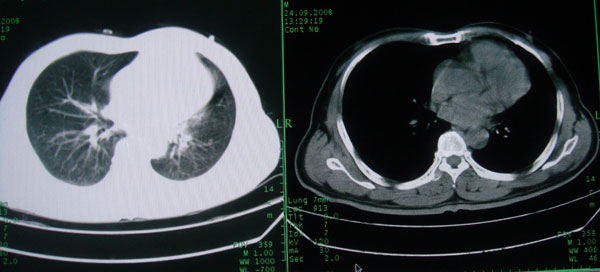

患者男性58岁因二周前起咳嗽,今天胸片示左上肺占位性病变行ct检查,无发热,无咯血痰.

左肺上叶病灶,实变但见含气支气管、空洞但未见壁内结节及积液;

考虑:①感染性病变(包括特殊感染型肺tb)

②肿瘤性病变(考虑患者年龄比较大的关系/所以不排除)

初学者。。。左肺空洞性病变,并可见阻塞性肺不张改变,鉴于患者为老年男性,且临床症状仅有咳嗽,全身中毒症状不明显,所以我首先考虑为左肺癌性空洞并左侧肺门淋巴结转移伴左肺阻塞性肺不张。结核性空洞放于第二位考虑,可以进行相关实验室检查。希望能有病理结果,谢谢!!!!!

左肺上叶实变影,内见支气管充气征及空洞影,病人年龄较大,无发热及结核中毒症状,心影左移,未见纵隔淋巴结肿大;不知实验室检查结果如何?有否嗜酸细胞增多,有没有进行治疗?就目前资料首先考虑1.感染性病变,2.慢性嗜酸性肺炎?可结合实验室检查并短期治疗复查,肺癌不能排除。